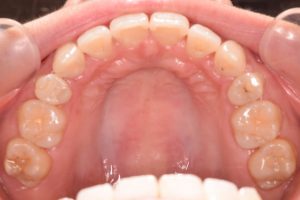

初診時(2022年12月)と装置撤去時(2025年9月)の写真です。

上あご

犬歯を咬合に参加させることで

奥歯に負担が掛からなくなります。

(犬歯誘導)

その後は順調に進み

2年5ヶ月で装置撤去できました。